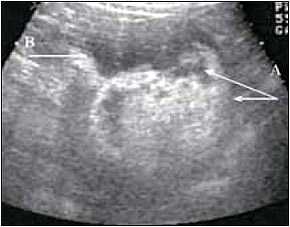

При ультразвуковом исследовании в проекции среднего и нижнего сегментов правой почки определяется гиперэхогенное образование до 9 см в диаметре, с четким контуром, целостность которого нарушена. В паранефральной клетчатке вокруг опухоли скопление анэхогенной жидкости в виде гематомы (рис. 1). Левая почка без патологических изменений. Заключение: ультразвуковая картина скорее всего соответствует спонтанному разрыву ангиомиолипомы правой почки.

Ультрасонограмма правой почки: А - анэхогенная жидкость, В - гиперэхогенное образование

Рис. 1. Ультрасонограмма правой почки: А - анэхогенная жидкость; В - гиперэхогенное образование.